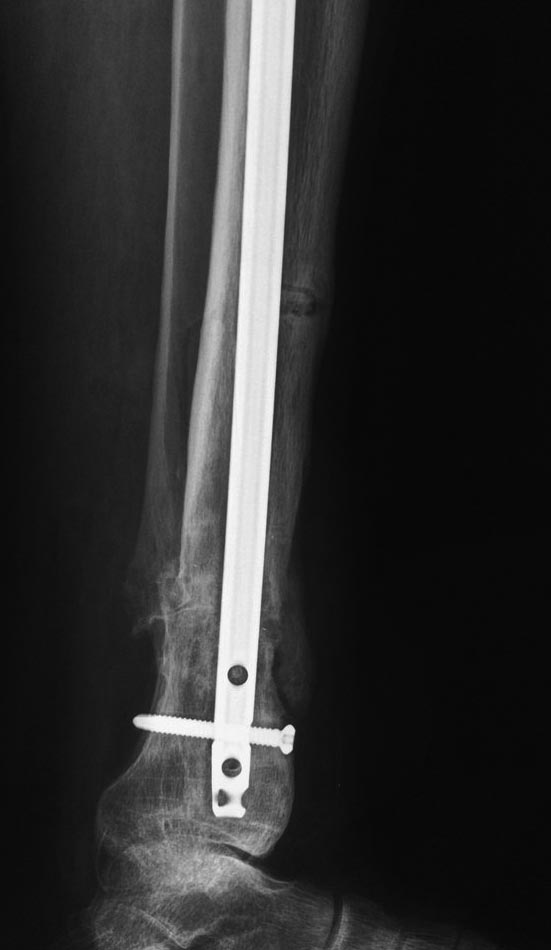

Уважаемые коллеги выразите Ваше мнение по следующему случаю. Молодой

человек, 27 лет, находится на лечении с диагнозом: Ложный сустав

большеберцовой кости в нижней трети, фиксированный интрамедуллярным

блокированным стержнем (12.02.2014 г), ложный сустав малоберцовой кости

в нижней трети левой голени, посттравматический артроз левого

голеностопного сустава 1 стадии. Укорочение левой нижней конечности на

В феврале 2014 г выполнил первым этапом: Фиксацию ложного

сустава в АНФ с восстановлением осей сегментов. Через семь дней БИОС с

рассверливанием.

После операции - вальгус голеностопного сустава. Гладкое течение

послеоперационного периода. Нагрузка по переносимости боли. Через 6

недель динамизация, через 2 недели стали мигрировать 2 фронтальных

винта. Пытался подкрутить, пришлось удалить.